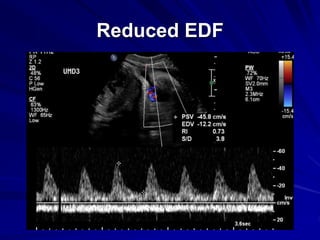

Reduced EDF

Absent EDF

Progress in placental failure

↓ umbilical artery EDF

↑ MCA flow

↓ aortic flow

Mod-severe redistribution

↓ growth

Abnormal venous flow

↓ FM

↓ LV

Abnormal CTG